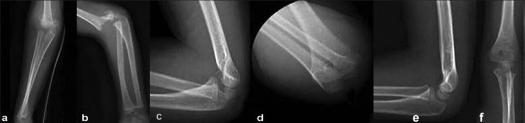

Retrospective data acquisition of 74 patients with a Gartland type II or type III fractures treated by closed reduction and immobilization (Blount's technique) between January 2004 and December 2007 was done. The mean age was 6.3 years (range, 2-11). The mean time of follow-up was 6.5 months (range, 3-25). All open injuries and complex elbow fracture dislocations or T-condylar fractures were excluded from the study. All patients were evaluated with standardized anteroposterior and true lateral x-rays of the elbow, and Flynn criteria were used for functional assessment.

Gartland type II fractures had 94% good or excellent final results. Gartland type III fractures had 73% good or excellent final result. The Gartland type III outcome depended on the displacement. The fractures remained stable in 88% for the posterior displacement, and 58% for the posteromedial displacement. These displacements were mild. However, for the posterolaterally displaced fractures, only 36% were stable; 36% had a mild displacement and 27% had a major displacement.

Pure posterior displacement is more stable than posteromedial displacement which is more stable than posterolaterally displaced fractures. This study suggests that Gartland type II and pure posterior or posteromedial displaced Gartland type III fractures can be treated by closed reduction and immobilization with success.